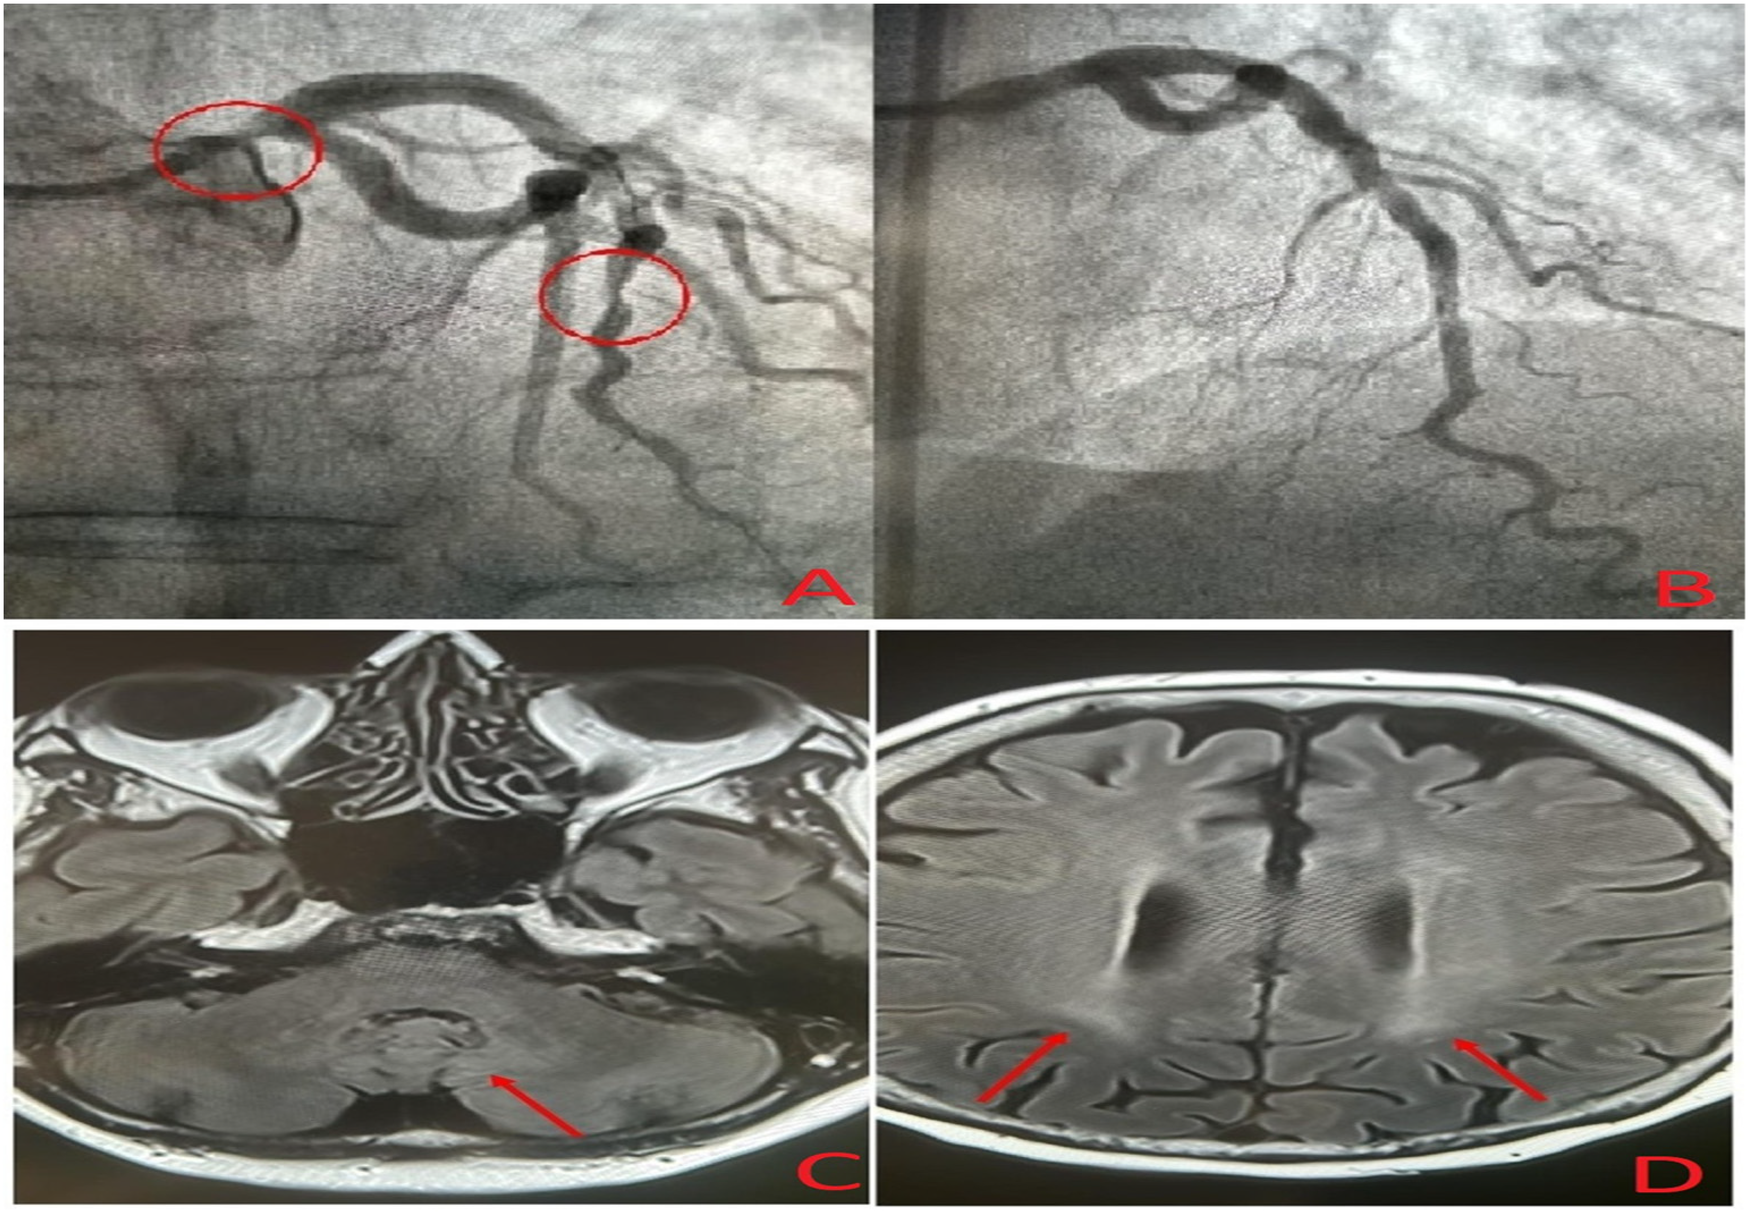

Figure 2

Coronary angiogram showing severe narrowing of the left main and left anterior descending coronary arteries (A), post-treatment coronary angiogram after percutaneous coronary intervention (B), and brain magnetic resonance imaging showing mild symmetrical FLAIR hyperintensities in the dentate nuclei (C) and periventricular white matter (D).

A 49-year-old woman who was previously healthy presented to the Department of Cardiology at Toulouse University Hospital for a cardiac evaluation. Her medical history included surgical excision of a large right Achilles tendon xanthoma for cosmetic reasons and walking difficulties. Histopathologic examination of the specimen revealed cholesterol crystals. On admission, she was asymptomatic with normal vital signs and without additional cardiovascular risk factors. Her physical examination revealed xanthelasma, bilateral xanthomas of the Achilles tendon and flexor tendons of the wrist, and xanthomas of the left extensor tendons of the hand (Figure 1). Blood tests revealed a total cholesterol level of 234 mg/dl (6.05 mmol/L), LDL-cholesterol level of 141 mg/dl (3.65 mmol/L), HDL-cholesterol level of 50 mg/dl (1.29 mmol/L), and triglyceride level of 188 mg/dl (2.12 mmol/L). Genetic testing for genes encoding for the LDL receptor, PCSK9, apolipoprotein B, and apolipoprotein E came back negative. Her coronary artery calcium score was 0 Agatston units. Her Dutch Lipid Clinic Network score was 8. The patient was diagnosed with HeFH and treated with a combination therapy of ezetimibe/simvastatin (10/20 mg/day). Two years later, during a scheduled follow-up, she underwent coronary angiography based on the clinical judgment of the cardiologist, despite an assessed coronary calcium artery score of 6 Agatston units on non-contrast cardiac CT and an LDL-cholesterol level of 77 mg/dl (1.99 mmol/L). Coronary angiography showed severe narrowing of the left main and third segments of the left anterior descending coronary artery (LAD), both of which were treated with percutaneous coronary intervention and stent implantation (Figure 2). The patient was lost to follow-up during the COVID-19 pandemic and was admitted 7 years later for myocardial scintigraphy-induced acute anterior ST-segment elevation myocardial infarction. After percutaneous revascularization of a severe LAD narrowing on the coronary angiogram, the transthoracic echocardiography reported a left ventricular ejection fraction of 34%. During the index hospital stay, her physical examination revealed mild cerebellar ataxia (unable to walk in a straight line with a broad-based gait) and a pyramidal syndrome (brisk reflexes and bilateral Babinski sign). The investigations were completed with a neuropsychological assessment, which showed a mild cognitive impairment with a dysexecutive syndrome (mainly attention deficit). Brain magnetic resonance imaging revealed mild symmetrical fluid attenuated inversion recovery (FLAIR) hyperintensities in the periventricular white matter and dentate nuclei (Figure 2). The diagnostic workup was advanced by quantifying plasma sterols, followed by sequencing the CYP27A1 gene. An elevated level of cholestanol (46 μmol/L; upper control limit 16 μmol/L) was found, and two likely pathogenic variants in exons 3 (c.470T>C, p. Leu157Pro) and 6 (c.1184G>A, p. Arg395His) of CYP27A1 were identified. Analysis of CYP27A1 transcripts in peripheral blood leukocytes showed the presence of at least three types of transcripts. The first transcript carried the c.470T>C (r.470u>c) variation. The second transcript contained the 1184 substitution (r.1184g>a) at the very end of exon 6 and the entire intron 6. This transcript would result in a truncated protein because of a frameshift and a premature stop codon (p. Arg395GlnfsTer2). The third transcript lacked the last (3′-terminal) 89 nucleotides of exon 6, leading to the loss of residues Val366 to Arg395 and resulting in a truncated protein due to a premature stop codon at residue 412. To confirm that the variant was likely in trans, segregation analysis was performed. The patient's mother eventually agreed to genetic testing and was found to be heterozygous for the c.1184G>A variant. Quantification of bile acids by LC–MS/MS showed undetectable levels of primary bile acids, while 7α-hydroxy-4-cholesten-3-one, a bile acid precursor and diagnostic marker of CTX, was found to be elevated (488 nmol/L vs. 25–100 nmol/L in controls). Consequently, the patient was diagnosed with CTX and discharged on chenodeoxycholic acid at a dose of 250 mg three times daily (Figure 3). After 1 year of treatment, the levels of primary bile acids and 7α-hydroxy-4-cholesten-3-one (39 nmol/L) normalized.